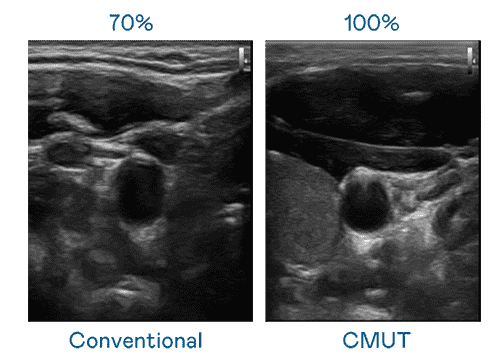

CMUT 技术是一种用电容式微机电元件来产生超音波讯号的技术。。。与传统 PZT 压电式技术相比,,,CMUT 频宽增加 30%,,,,更宽频的超音波讯号让影像解析度大幅提升,,,,是实现高影像品质医疗超音波扫描、、、促进精准医疗发展的关键技术。。。

大频宽带来超清晰影像

超音波影像的解析度高低,,,,首先取决于探头能发出的讯号频宽。。尊时凯龙 CMUT 可提供高清晰的超音波讯号,,提供高频宽、、、高灵敏度、、、影像纹理细节更高的超音波影像,,,协助医护人员缩短影像判读时间及利用精准的医疗影像进行诊断。。。